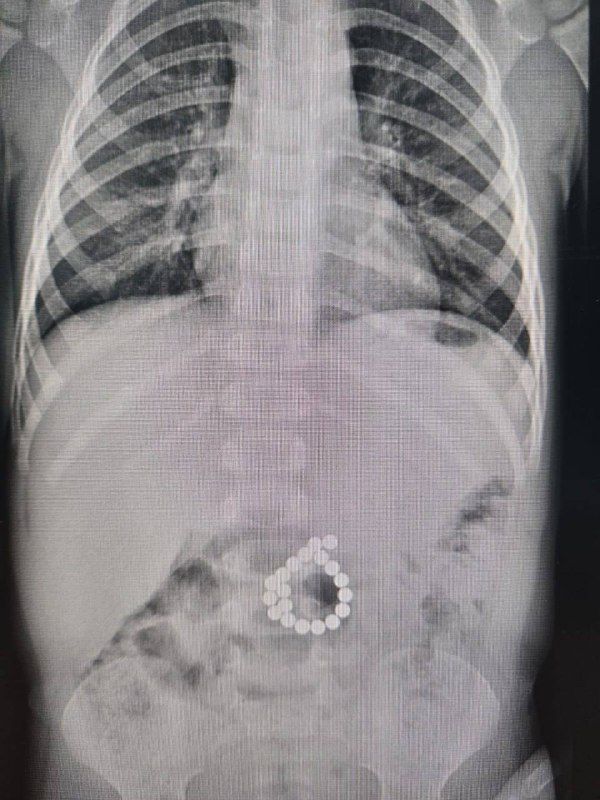

В Центр охраны материнства и детства поступил двухлетний мальчик с жалобами на сильную боль в животе, высокую температуру. Мама рассказала, что за два дня до появления острых болей в животе сын играл с магнитным конструктором.

«То, что врачи увидели, подтвердило опасения: 19 магнитов, оказавшихся в толстой кишке, сомкнулись, буквально «прокусив» стенку. В результате возникла двойная перфорация стенки кишки – крайне опасное, жизнеугрожающее состояние, которое привело к развитию инфекции и воспаления брюшной полости», - рассказали в пресс-службе Центра охраны материнства и детства.